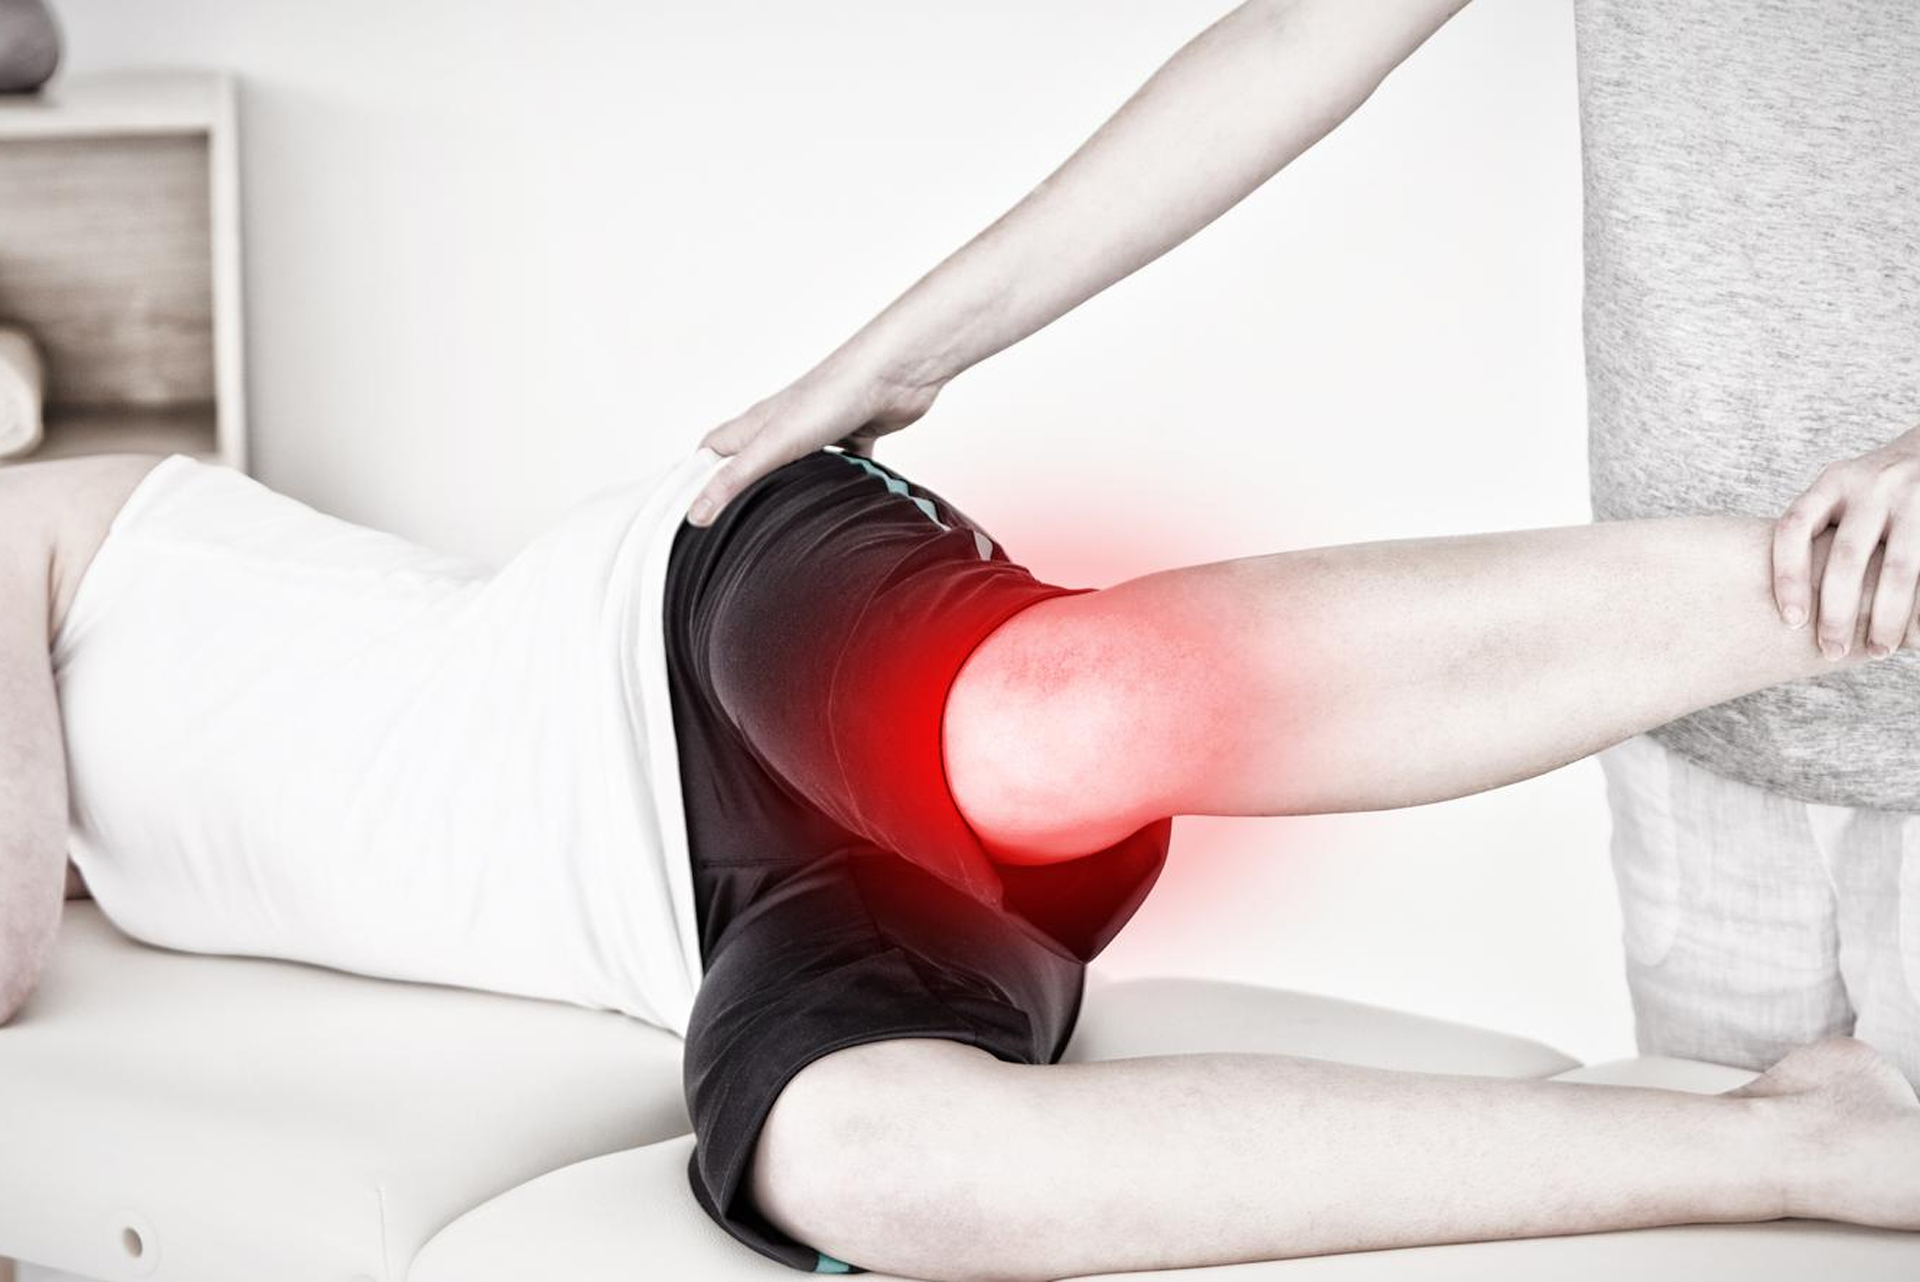

Die Physiotherapie spielt eine zentrale Rolle im Gesundheitswesen, indem sie darauf abzielt, die Bewegungsfähigkeit des Körpers wiederherzustellen und…

Physiotherapie ist ein zentraler Bestandteil des modernen Gesundheitswesens und umfasst eine Vielzahl von therapeutischen Maßnahmen, die darauf abzielen,…